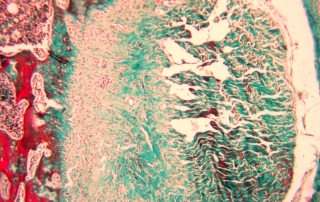

la première version de la formation en Histologie, Histochimie et Immunofluorescence organisée par l’AT-PNEI. Merci à tous les organisateurs, les formatrices et les participantes